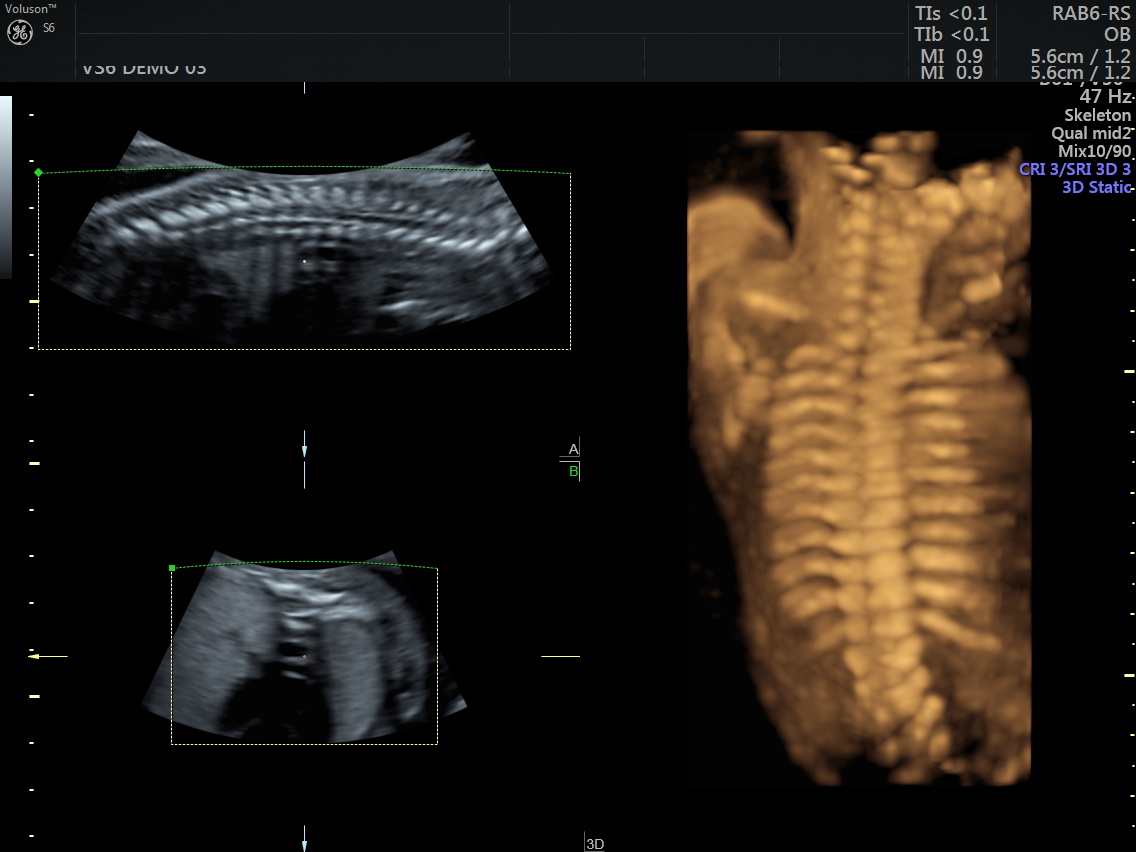

4 Boyutlu Renkli Ultrason

4D (dört boyutlu), Renkli, Ayrıntılı Gebelik Ultrasonu

4 boyutlu renkli ultrason cihazı ile çok erken dönemde cinsiyet, yarık dudak, yarık damak, eksik parmak, beyin ve omurilikten kaynaklanan rahatsızlıkların erken tanısı konulabiliyor.